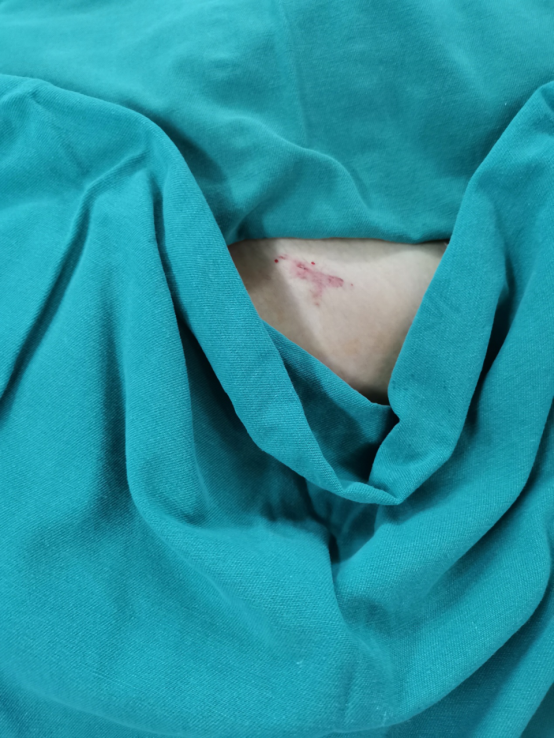

由于在传统手术方式中,为确保骨折固定置入螺钉位置的准确性,往往需要作大切口,术中医生还需要反复透视定位查看置钉位置,不仅创伤大、时间长,X线辐射暴露次数也很多。因此,团队为菲菲制定了微创手术方案,术中团队精准定位、精细操作,手术切口仅2厘米,出血不到10ml,一期为菲菲完成了左侧骨盆骨折内固定手术,术后恢复顺利。

▲微创切口仅2㎝